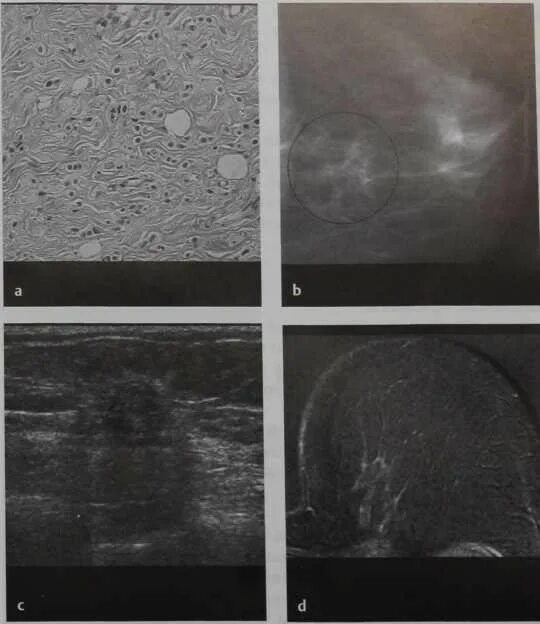

Метастазы в молочную железу